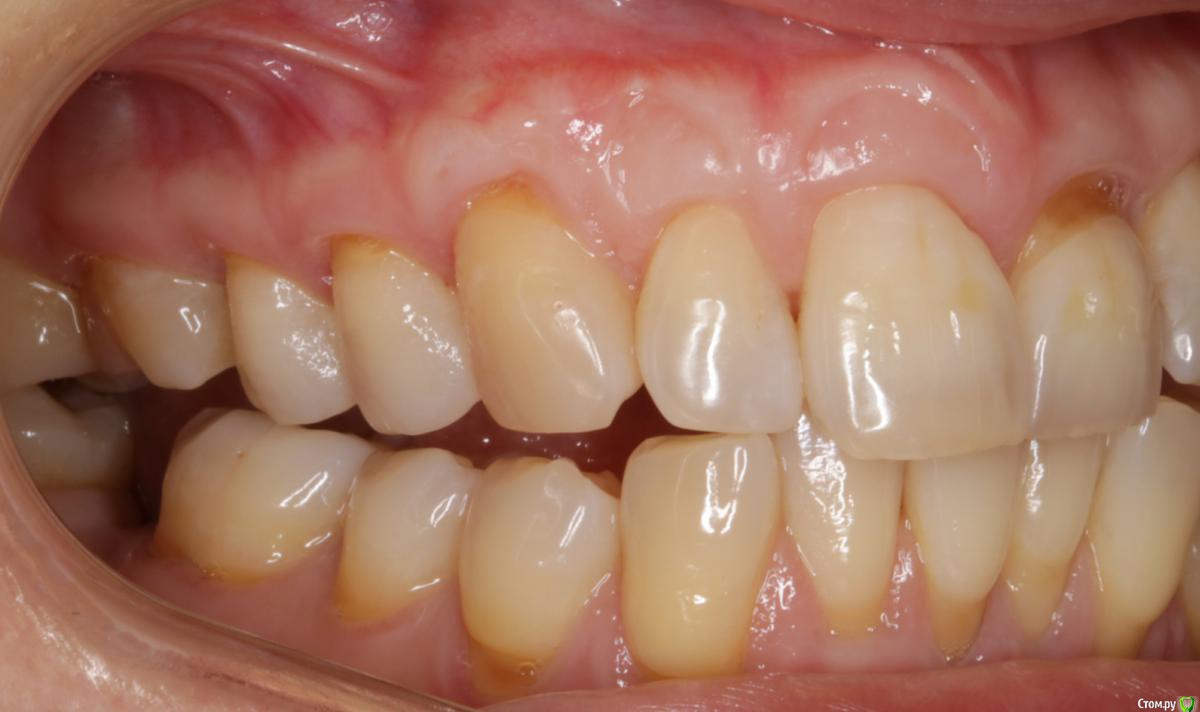

Dmitry DK Опубликовано 31 августа, 2019 Поделиться Опубликовано 31 августа, 2019 Доброго дня! Первичное обращение пациентки было связано с отсутствием 25 зуба, эстетические нарушения слизистой, клиновидные деф-ты в области других зубов - не смущали.В итоге решили, раз проводим операцию ( импл + ССТ ), закроем попутно и рец на верхней челюсти.Реставрацию на 21 зуб все не ставит... Приятных тебе выходных! ) Пациентка проходила лечение 2,5 года назад, пришла на проф осмотр 7 Ссылка на комментарий

Bier Опубликовано 3 сентября, 2019 Поделиться Опубликовано 3 сентября, 2019 в итоге наврали с зенитом на имплантате. Ссылка на комментарий

Bier Опубликовано 3 сентября, 2019 Поделиться Опубликовано 3 сентября, 2019 что вы имеете ввиду?короткий зуб, что же еще. Ссылка на комментарий

Dmitry DK Опубликовано 4 сентября, 2019 Автор Поделиться Опубликовано 4 сентября, 2019 короткий зуб, что же еще.У имплантата край дёсны действительно корональнее.Платплатформа в двух миллиметрах от цементо-эмалевой границы, была возможность иссечь излишек либо его ещё отдавить, также как хотелось заполировать в 1-м сегменте, поставит реставрацию на 21-м и т.д.Пациентка отказалась от дальнейших этапов... Ссылка на комментарий